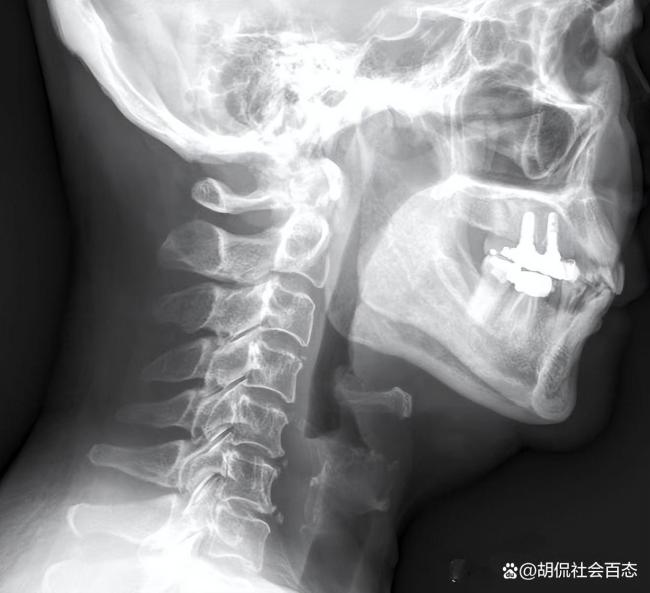

司法鉴定结论明确:杨某的死亡是因鱼刺刺伤咽喉,引发急性喉头水肿、出血及急性炎症,进而阻塞呼吸道,最终因缺氧窒息导致。此外,鉴定还提到财富e99,其自身的糖尿病基础疾病、自行不当处置以及精神紧张等因素叠加,加剧了病情的发展,这也解释了为何看似常见的鱼刺卡喉会引发如此凶险的后果。